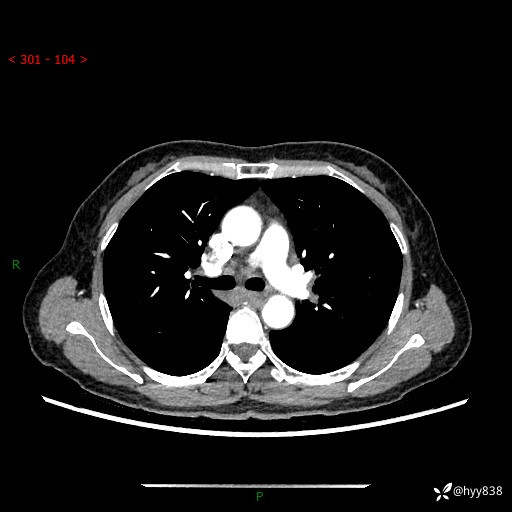

【患者信息】:58岁/女

【主诉】:体检发现肺结节

【检查】:胸部CT平扫+增强